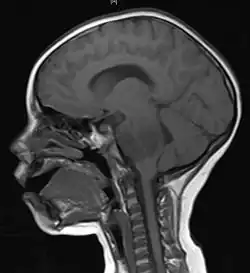

Meninges

Human brains are surrounded by a system of connective tissue membranes called meninges that separate the brain from the skull. This three-layered covering is composed of (from the outside in) the dura mater, arachnoid mater, and pia mater. The arachnoid and pia are physically connected and thus often considered as a single layer, the leptomeninges. Between the arachnoid mater and the pia mater is the subarachnoid space which contains cerebrospinal fluid (CSF). This fluid circulates in the narrow spaces between cells and through the cavities in the brain called ventricles, to support and protect the brain tissue. Blood vessels enter the central nervous system through the perivascular space above the pia mater. The cells in the blood vessel walls are joined tightly, forming the blood–brain barrier which protects the brain from toxins that might enter through the blood.[35]

Brain matter

The three largest divisions of the brain are the cerebral cortex, cerebellum and the brainstem.[35] These areas are composed of two broad classes of cells: neurons and glia. These two cell types are equally numerous in the brain as a whole, although glial cells outnumber neurons roughly 4 to 1 in the cerebral cortex. Glia come in several types, which perform a number of critical functions, including structural support, metabolic support, insulation, and guidance of development.[37] Primary tumors of the glial cells are called gliomas and often are malignant by the time they are diagnosed.[38]

The thalamus and hypothalamus are major divisions of the diencephalon, with the pituitary gland and pineal gland attached at the bottom; tumors of the pituitary[39] and pineal gland[40] are often benign.

The brainstem lies between the large cerebral cortex and the spinal cord. It is divided into the midbrain, pons, and medulla oblongata.[35]